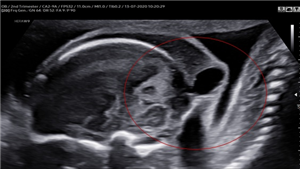

Fetus in Fetu (FIF) là bất thường rất hiếm gặp của song thai một trứng, trong đó một thai không trưởng thành sống ký sinh trong cơ thể của thai bình thường